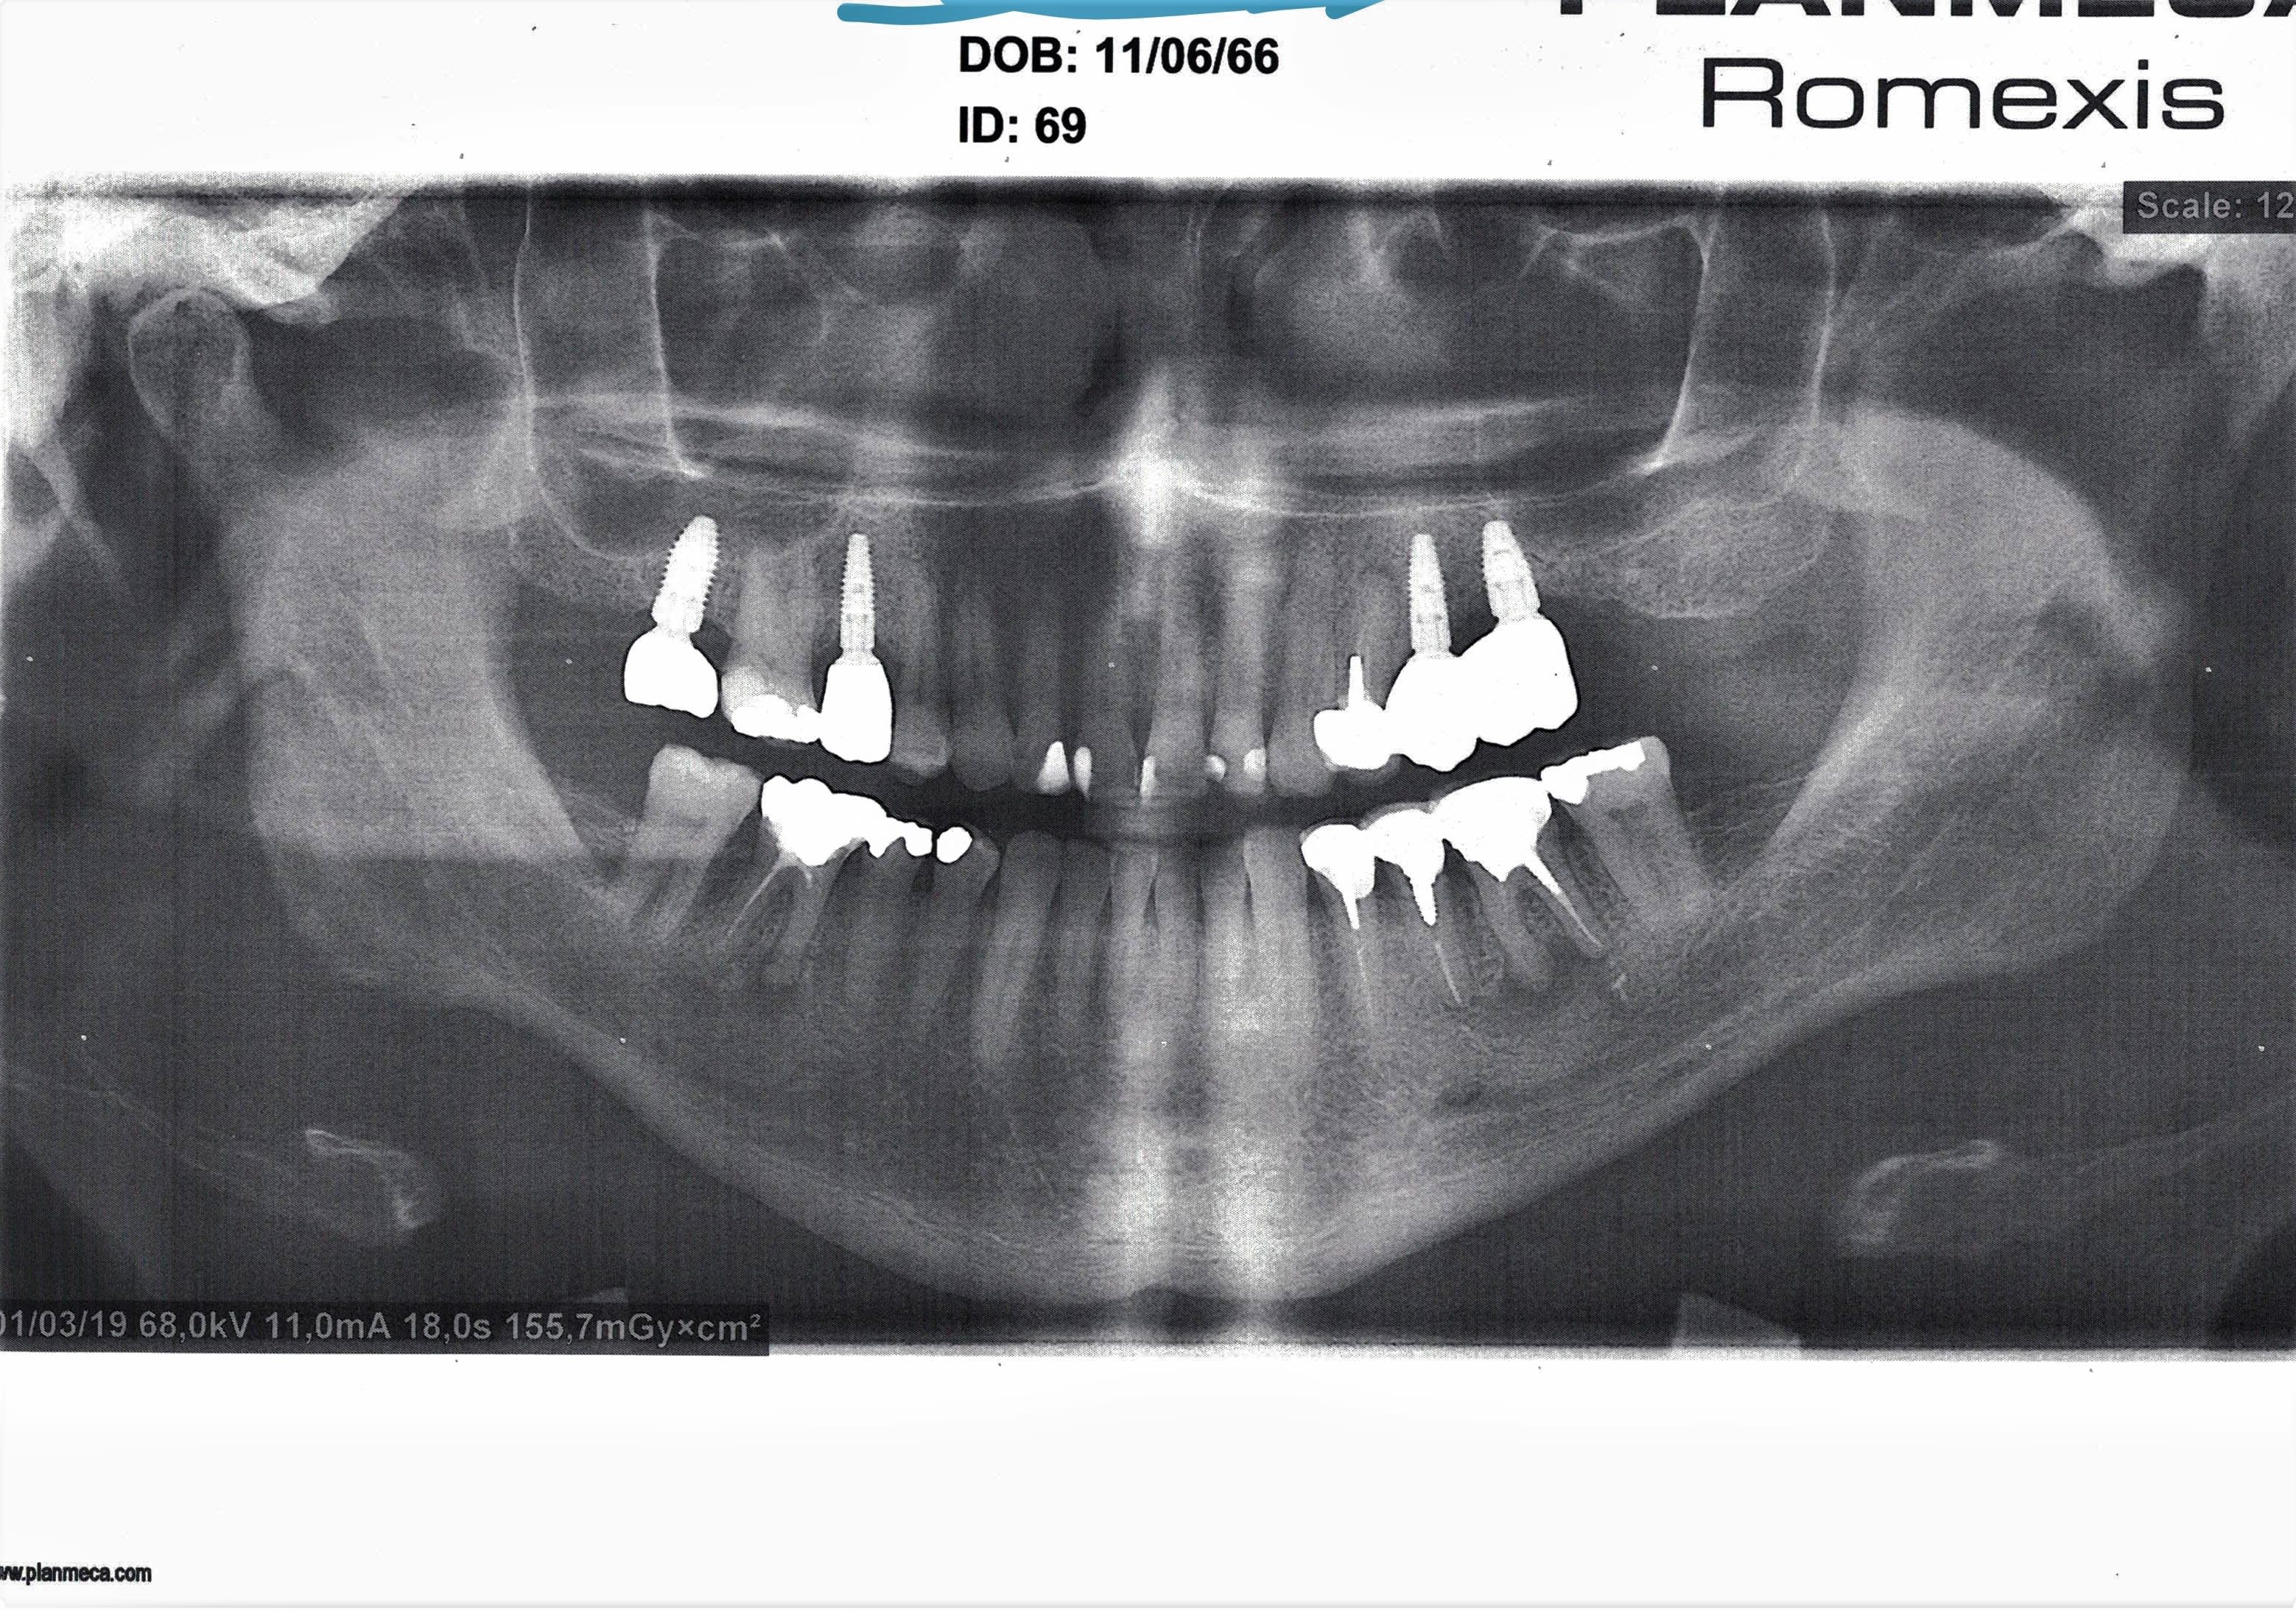

la suite

pano faite en mars 2019

couronne posée en aout 2019

la dent à bien ingressé le patient n'est pas mytho: si vous regardez le contour osseux autour de la 16, il est supérieur aux dent adjacentes du fait de la cratérisation autour des implants.

Sur la rétro le contour osseux sur la 16 est en dessous des implants

Je reviens après, mais y'a un truc qui me marque: sur la pano, la palatine de la 6 est à peine au contact du sinus, sur les rétros elle est complètement dedans.

L'angulation peut jour, mais...

tu as vu que sur la pano , la 6 n as pas plus d espace ligamentaire que sur les retro d après ?